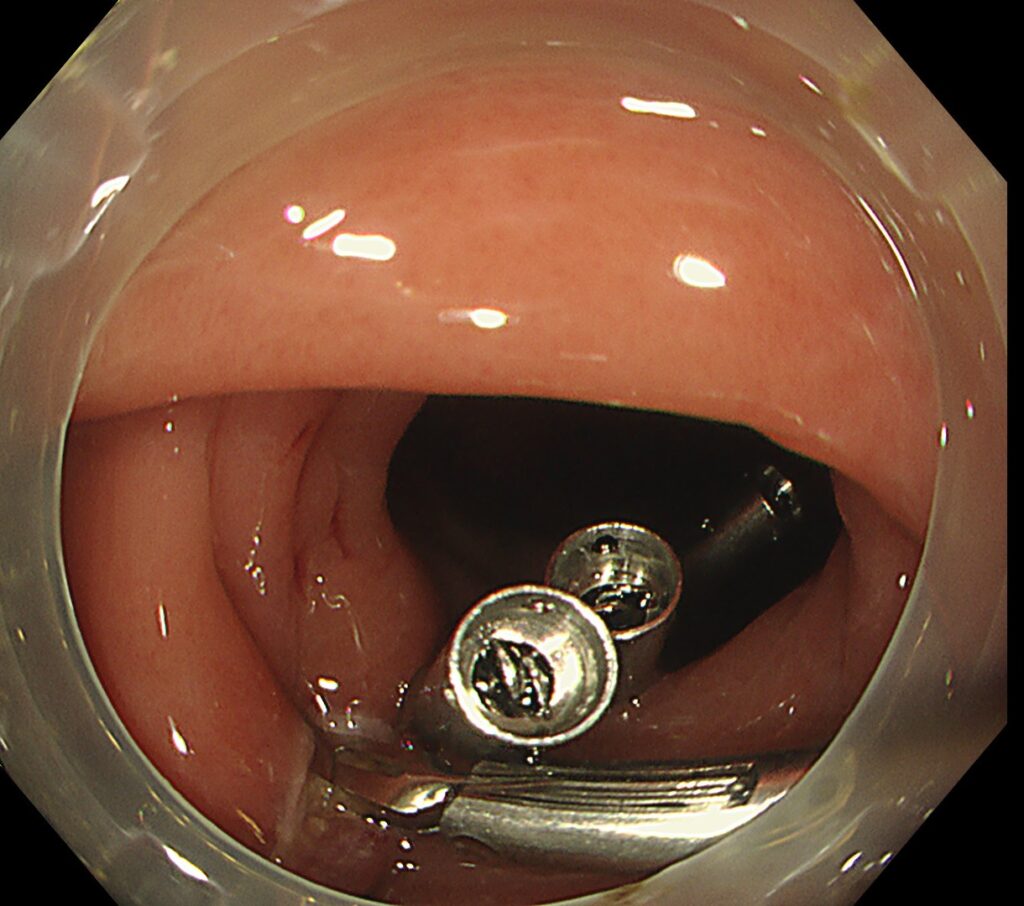

上図の如く、腫瘍辺縁にマーキングをおき、腫瘍サイズが大きいため、ポケット法による切除を選択しました。

腫瘍の遠位側に、メスをいれて、粘膜下層を充分トリミングします。